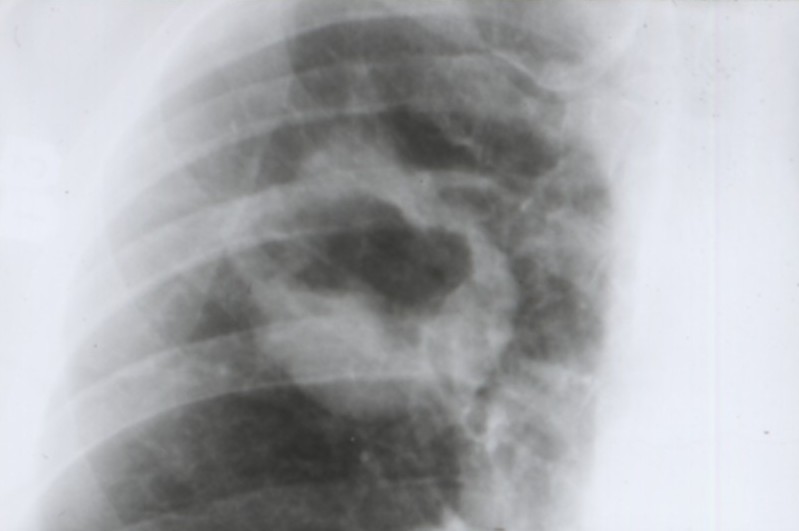

Cancers bronchiques